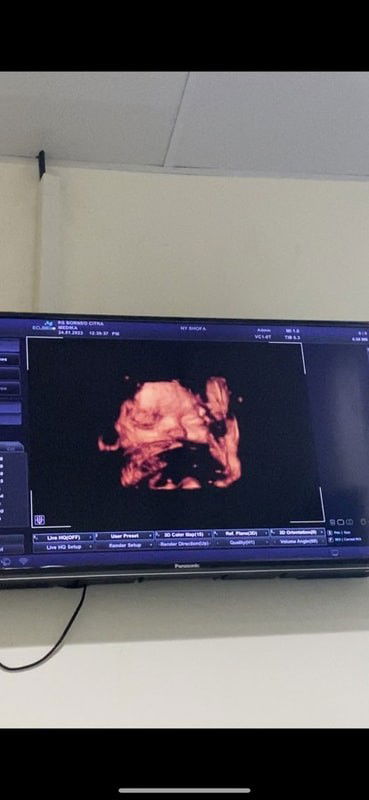

Alhamdulillah bun udah lahiran. Pembukaan dri jm 11 mlm smpai 4 sore masih 2 jd induksi infus dan telah lahir putri pertama kami di tgl 13-032023 BB 3.1kg usia kandungan 38mg 3hari🤲🏻😇perjuangan yg masyaallah krna udah gk kuat ngeden ibu nya jd divakum ngeden trakhir sampe pendarahan+bonus jahitan☺️ #firstmom